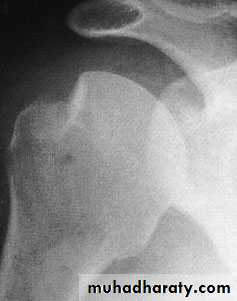

Imaging

x-ray: The Hill–Sachs lesion (when it ispresent) is best shown by an anteroposterior x-ray with the shoulder internally rotated, or in the axillary view. Subluxation is seen in the axillary view.MRI or MR arthrography: bone lesions and labral tears.